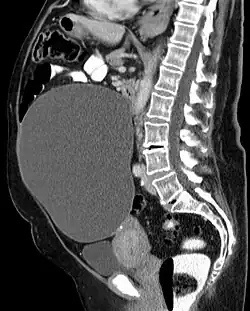

Ein Zystom (auch Kystom, Kystadenom und Cystadenom, und erstmals 1889 Proliferationszyste[1] genannt) ist eine Drüsengeschwulst, in der sich aufgrund von nichterfolgtem Abfluss des Drüsenproduktes ein Hohlraum bildet.

Zystome sind gutartig, eine Entartung ins Krebsartige geschieht vor allem dann, wenn papillare Wucherungen enthalten sind. Zystome treten am häufigsten in Eierstöcken, Nieren, Brustdrüsen, Leber und Schilddrüsen auf. Auch in der Bauchspeicheldrüse[2] können sie vorkommen.